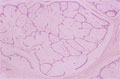

• š(2)Fibroadenoma(intracanalicular type)

Macroscopic image:Firm, rounded and whitish tumor surrounded by thin capsule.